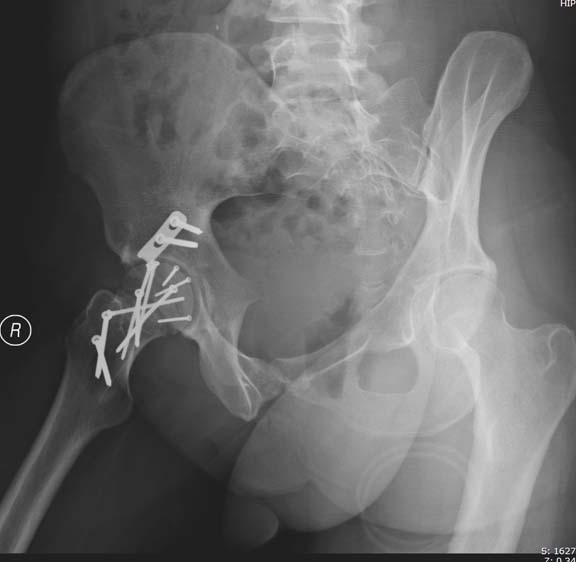

Далее перевод к нам в Травмоцентр и 03.03.2015. через 8 дней операция, выполнен остеосинтез головки 3-мя самокомпрессирующими винтами Autofix под разными углами с погружением в субхондральный слой. Доступ Kocher-Langenbeck с флип-остеотомией большого вертела и задним хирургическим вывихом головки бедра. В полости сустава два свободно-лежачих фрагмента хряща головки, которые были удалены. На снимках виден дефект хряща головки после репозиции. Небольшой фрагмент заднего края фиксирован двумя спонгиозными винтами. Далее шов раны с дренированием. На 2 сутки пациент поворачивался на здоровый бок с валиком между ног, на 4 сутки сидел в кровати и на 6 сутки ходил с помощью костылей.

Здесь выбрана правильная тактика и операция сделано на хорошо. Надеюсь, промах с фиксацией не создаст проблему. Можно было добавить в задную стенку spring plate и винты до медиального кортекса в фиксации вертела.

Здесь клинические примеры: Первый случай передний доступ, второй с ICP monitor Flipp Trochanteris

и с переломом заднего края.